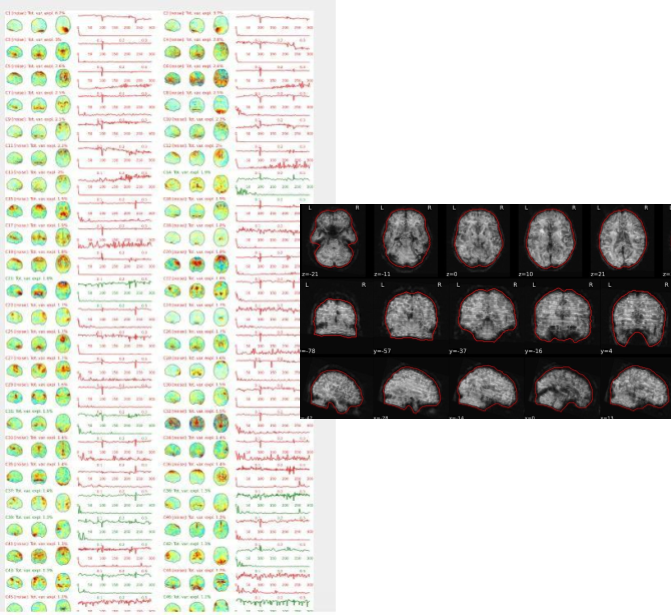

EPI confounds (carpet plot)

A carpet plot is a 2D ‘heatmap’ of relevant time series within a scan, with voxels on the vertical axis and time on the horizontal axis. Voxels are grouped into blue=cortical GM, orange=subcortical GM, green=cerebellum, red=white matter and CSF, as indicated by the colour map on the left-hand side of the plot.

In the carpet plot it is important to look for changes in heatmap/intensity and how they relate to motion (frame-wise displacement (FD)) and global signal (GS) measures (the graphs above the carpet plot). Unusual changes might represent other artefacts (e.g., hardware related) or changes in respiratory patterns.

Example of a good subject

- No changes in the heatmap, low motion (FD mean < 0.5), no sudden large jumps in the FD line or GS

- Small changes in the heatmap identifiable as caused by motion or other causes (i.e., corresponding to changes in the graphs above the heatmap)

Example of an uncertain subject

Example of a bad subject

- Large changes in the heatmap can be indicative of motion. If this is the case, they will usually correspond to changes in the FD line (purple line) above the heatmap. Mean FD and max FD are also reported in the plot for each subject

- For group analysis, there will be the option to automatically exclude subjects with mean FD > 0.5, so you don’t have to check the mean FD for all subjects at this stage (but it could be helpful to look at FD values if you are unsure about whether to exclude or not a subject). Although we have not included a hard threshold for max FD, values > 3mm could be indicative of a problematic subject (i.e., with sudden jumps). In data sets with a high percentage of high motion individuals, it is worth considering whether the threshold should be raised to >3.5mm, in order to include a larger percentage of subjects.

- Changes in the heatmap without clear causes may indicate other artefacts, such as hardware-related artefacts. Other sudden changes could be related to respiratory patterns

- If you think that the carpet plot shows artefacts or other problematic issues, check the other quality metrics for that subject to decide whether they should be excluded

Summary

| good | bad |

|---|---|

| No changes in the heatmap | Big changes: - could be related to motion (change in the FD-line) |

| Small changes in the heatmap caused by motion mean FD < 0.5 | Mean FD > 0.5 or maximum FD > 3 mm |

| DVARS and FD “similar” | |

| No big spikes |